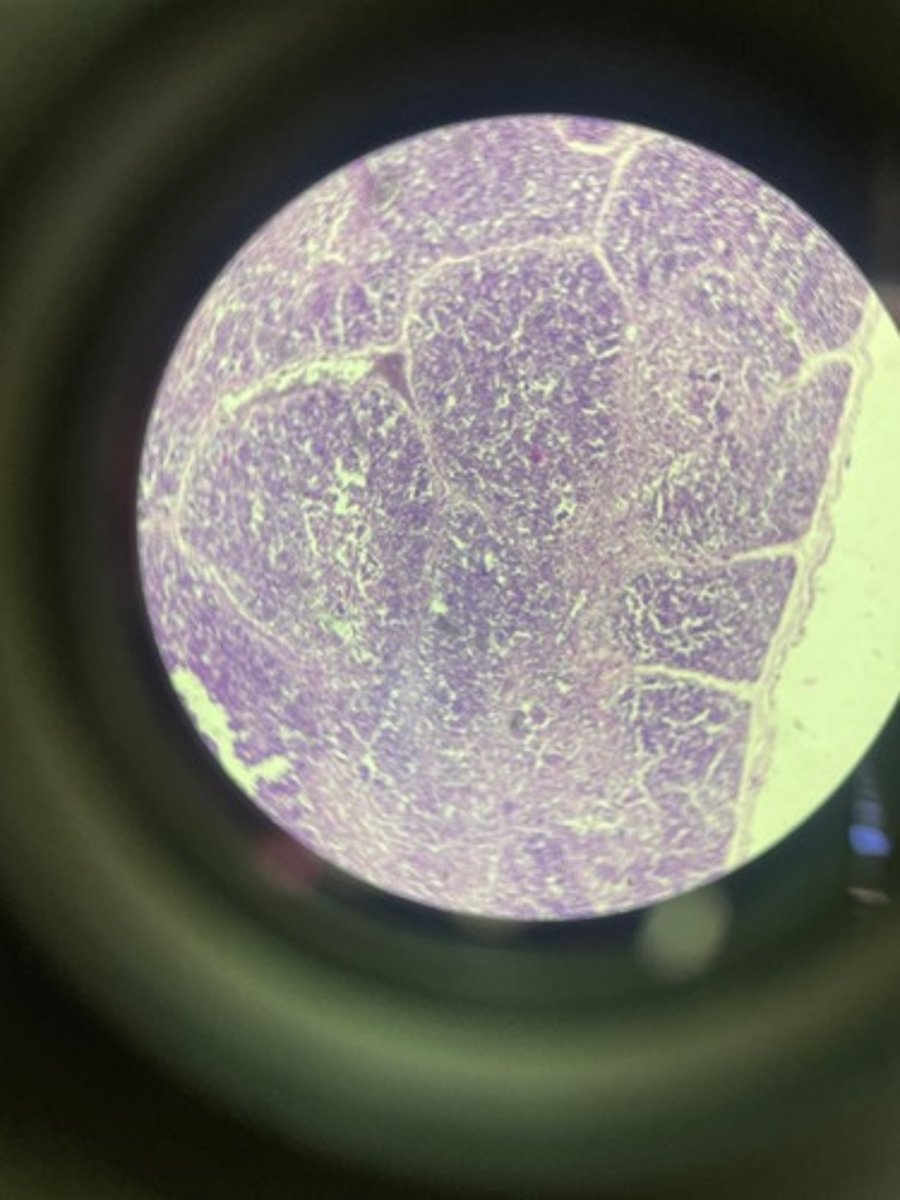

Thymus HE

Thymus HE

Thymus HE

Thymus HE

Thymus HE

Thymus HE

Thymus HE

Thymus HE